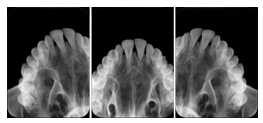

Intra-oral radiography typically involves acquisition of multiple images of various parts of the dentition. Many digital radiographic systems offer customized templates that are used for displaying the images in a study on the screen. These templates may also be referred to as mounts or view sets. The Structured Display Object represents a standard method of encoding and exchanging the layout and intended display of Structured Displays. A structured display object created in this manner could be stored with a study and exchanged with images to allow for complete reproduction of the original exam.

1. A patient visits a General Dentist where a Full Mouth Series Exam with 18 images is acquired. The dentist observes severe bone loss and refers the patient to a Periodontist. The 18 images from the Full Mouth Series along with a Structured Display are copied to a DICOM Interchange CD and sent with the patient to see the specialist. The Periodontist uses the CD to open the exam in his Dental Radiographic Software and consults via phone with the General Dentist. Both are able to observe the same exam showing the images on each user's display using the exact same layout.

Intra-oral Full Mouth Series Structured Display

Figure OO-1. Intra-oral Full Mouth Series Structured Display